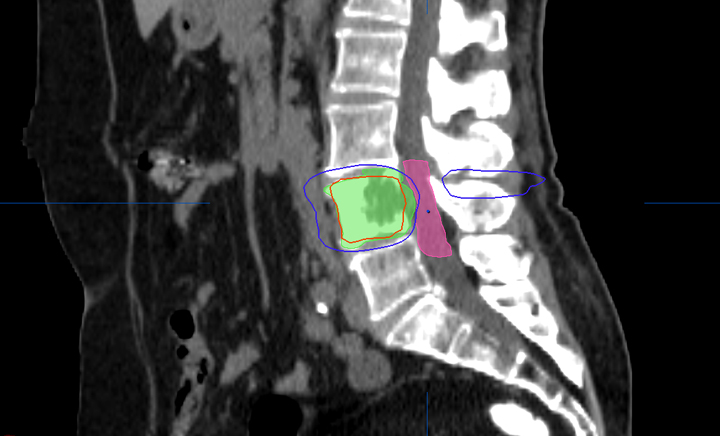

Radioterapia en las metástasis óseas

13 febrero 2017

El 40% de los pacientes tuvo reducción del dolor y mejor calidad de vida a los 10 días de iniciar el tratamiento. Se debe ofrecer radioterapia para las metástasis óseas a todos los pacientes, incluso a aquellos con una supervivencia pobre. JAMA Oncology, 9 de febrero de 2017